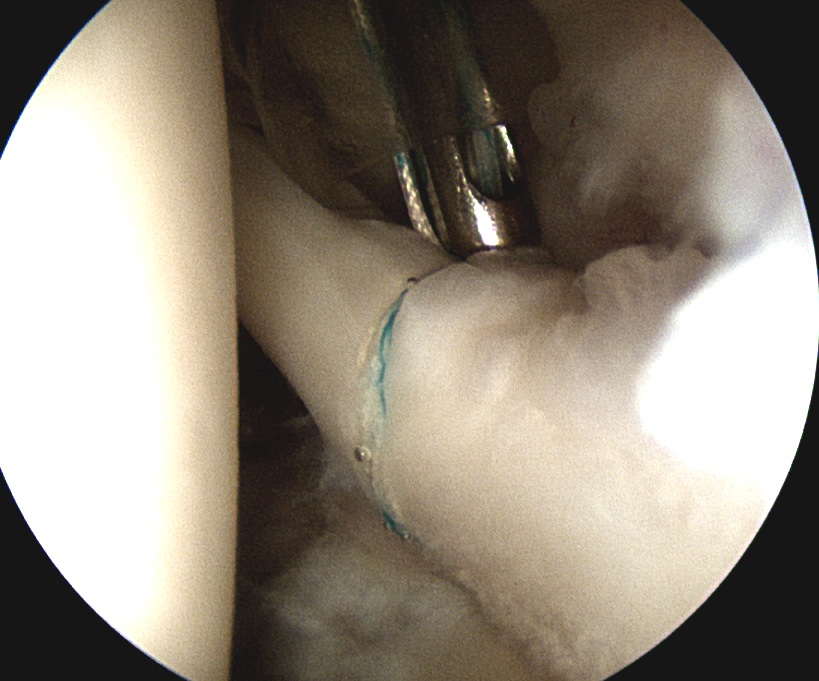

2. Prepare insertion

- shaver via anterior portal

- debride frayed labrum

- mobilise biceps tendon

- debride bony base to create ledge and bleeding bone